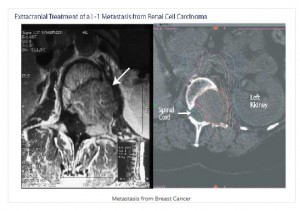

Η θεραπευτική επιλογή εξαρτάται από τον ιστολογικό τύπο της νόσου, το μέγεθος της βλάβης, τον αριθμό των βλαβών και την θέση τους, την παρουσία συμπτωμάτων, την εξωκρανια νόσο, την ηλικία, την κατάσταση ικανότητας του ασθενούς και τις προηγούμενες θεραπείες.

Έτσι απαιτείται σωστός συγχρονισμός των θεραπευτικών χειρισμών που περιλαμβάνουν το χειρουργείο, την ακτινοχειρουργική και την ολοκράνια ακτινοβολία.